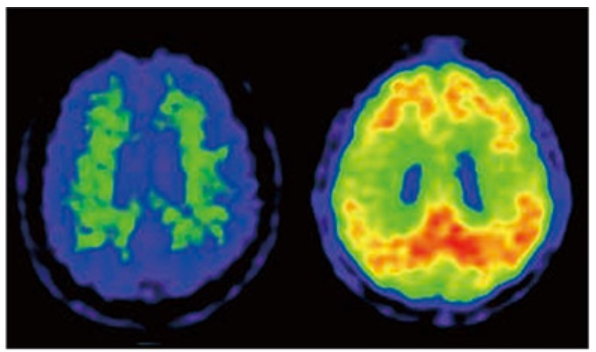

다음으로 뇌혈류SPECT스펙또는 뇌FDG-PET에프디지 애완동물에 의해 뇌의 기능을 진단합니다. 뇌 FDG-PET 쪽이 뇌혈류 SPECT보다 예민하게 기능 이상을 파악할 수 있습니다만, 현재, 아직 건강 보험 적용이 되어 있지 않기 때문에 자유 진료로 뇌 FDG-PET를 실시하는지, 건강 보험 진료로 뇌 혈류 SPECT를 수행합니다. 뇌 혈류 SPECT 및 FDG-PET를 수행하면 알츠하이머 병에서 뇌에정수리 연합야도초렌고우야, 측두 연합야,후부 띠 모양 회고부타이 조카이·쐐기 정면세츠젠부라고 하는 부위에서 혈류나 당 대사가 저하하고 있는 것을 알 수 있습니다(화상 2). 진행하면 전두 연합야의 혈류·대사도 저하해 옵니다. 이러한 소견을 발견함으로써 알츠하이머병을 조기에 발견하거나 다른 치매를 일으키는 질환과 감별합니다.

오른쪽 사진 : 정상자와 알츠하이머병의 뇌 FDG-PET

정상자에서는 뇌의 포도당 대사의 저하는 없습니다만, 알츠하이머병에서는 조기의 단계에서는 두정엽의 대사의 저하가 보입니다(↑)